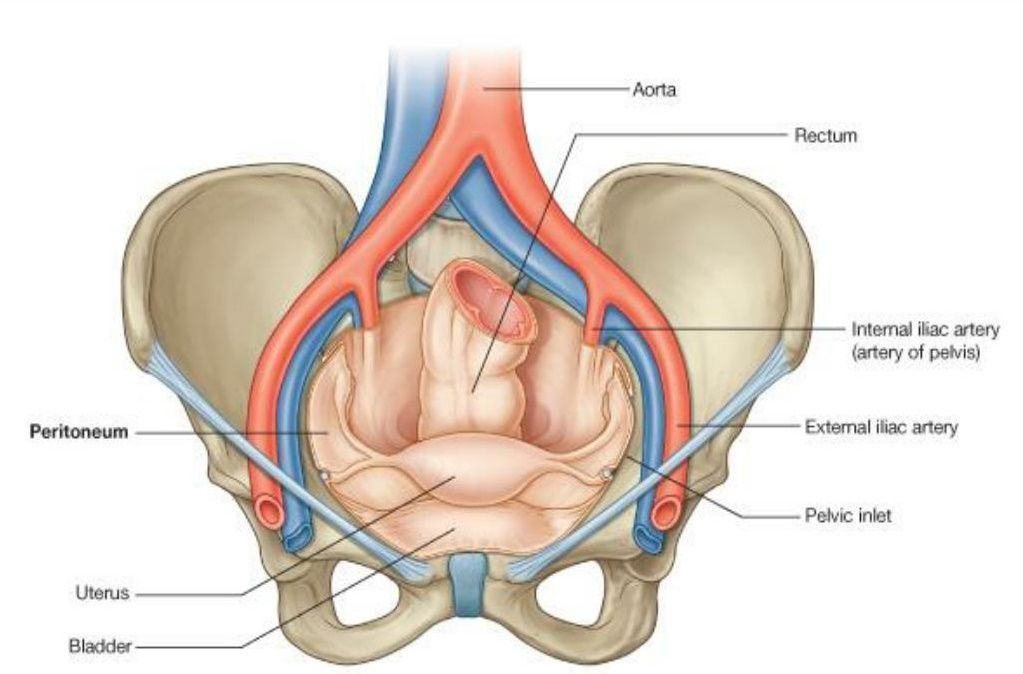

Анатомия малого таза: детальные схемы и изображения